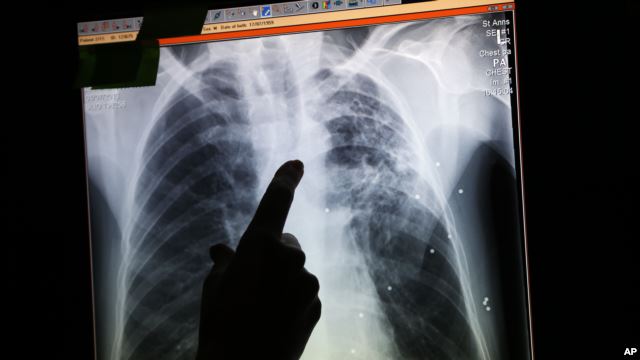

Giới nghiên cứu y khoa vừa phát hiện ra rằng ung thư phổi có thể kéo dài âm ỉ trên 20 năm trước khi đột ngột trở thành tử thần cướp đi mạng sống con người.

Phim X quang của một bệnh nhân bị ung thư phổi

Các chuyên gia viết trên tạp san khoa học Science rằng điều này giúp giải thích nguyên nhân vì sao ung thư phổi rất khó chữa trị.

Các nhà nghiên cứu cho biết điều mà họ gọi là lỗi gene có thể không bị phát hiện trong nhiều năm trước khi một lỗi khác thình lình kích thích ung thư phổi phát triển nhanh chóng.

Các chuyên gia nói hút thuốc lá là nguyên nhân chính của lỗi gene ban đầu và rằng cuộc nghiên cứu có thể giúp hiểu rõ ung thư phổi tiến triển ra sao.

Ung thư phổi là dạng bệnh phổi gây chết người cao nhất trên thế giới. Các bác sĩ nói tỷ lệ sống sót của ung thư phổi hết sức thấp.